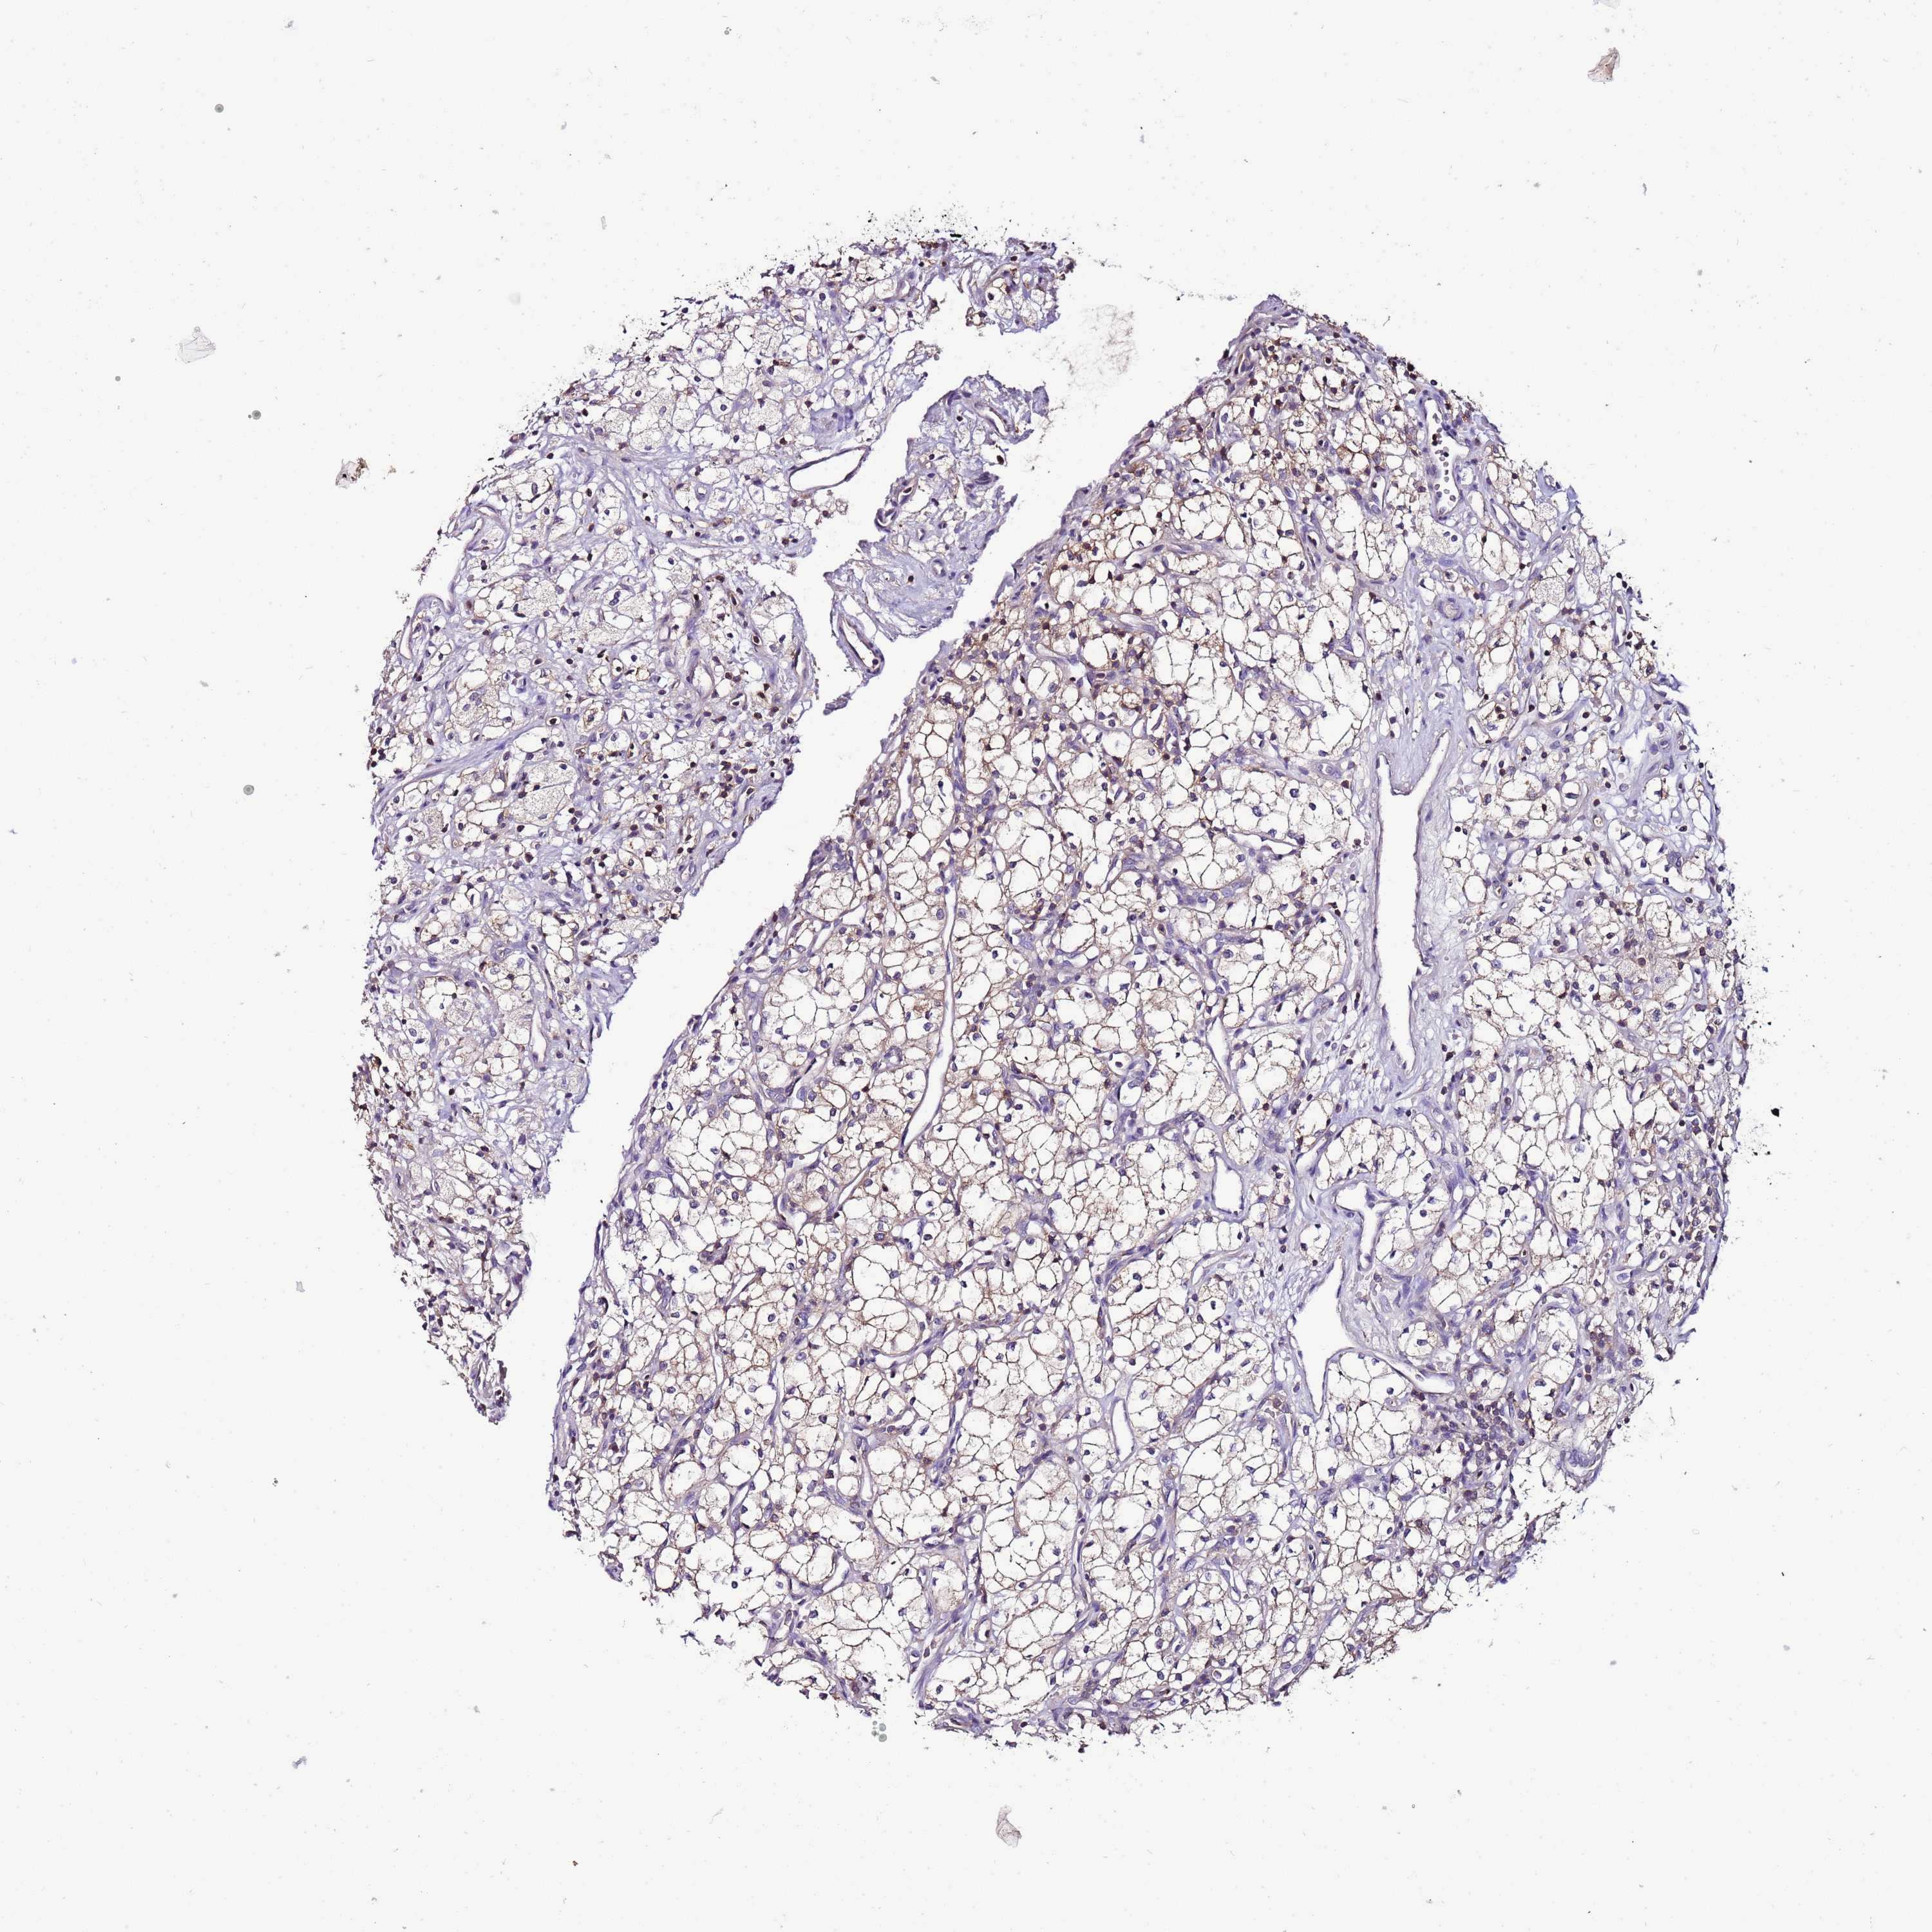

KIDNEY CHROMOPHOBE (TCGA) - Interactive survival scatter ploti

The Survival Scatter plot shows the clinical status (i.e. dead or alive) for all individuals in the patient cohort, based on the same data that underlies the corresponding Kaplan-Meier plots. Patients that are alive at last time for follow-up are shown in blue and patients who have died during the study are shown in red.

The x-axis shows the expression levels (FPKM) of the investigated gene in the tumor tissue at the time of diagnosis. The y-axis shows the follow-up time after diagnosis (years). Both axes are complimented with kernel density curves demonstrating the data density over the axes. The top density plot shows the expression levels (FPKM) distribution among dead (red) and alive patients (blue). The right density plot shows the data density of the survived years of dead patients with high and low expression levels respectively, stratified using the cutoff indicated by the vertical dashed line through the Survival Scatter plot. This cutoff is automatically defined based on the FPKM cutoff that minimizes the p-score. The cutoff can be changed by dragging the vertical line or by entering a cutoff value in the square labeled "Current cut-off".

Under the Survival Scatter plot the p-score landscape (black curve; left axis) is shown together with dead median separation (red curve; right axis). Dead median separation is the difference in median mRNA expression between patients who have died with high and low expression, respectively. It is calculated as follows: median FPKM expression of dead patients with high expression - median FPKM expression of dead patients with low expression. This is intended to aid the user in visually exploring custom cutoffs and the associated p-scores and dead median separation.

Individual patient data is displayed and can be filtered by clicking on one or more of the category buttons on the top of the page. Categories describing expression level and patient information include: high, low, alive, dead, female, male and tumor stages. The scale of the x-axis can be toggled between linear and log-scale by clicking on the "x log" button. Mouse-over function shows TCGA ID, patient information and mRNA expression (FPKM) for each patient.

& Survival analysisi

Kaplan-Meier plots summarize results from analysis of correlation between mRNA expression level and patient survival. Patients were divided based on level of expression into one of the two groups "low" (under cut off) or "high" (over cut off). X-axis shows time for survival (years) and y-axis shows the probability of survival, where 1.0 corresponds to 100 percent.

IGIP is not prognostic in Kidney Chromophobe (TCGA)

: 9.02

Average pTPM 7.2

Number of samples 64